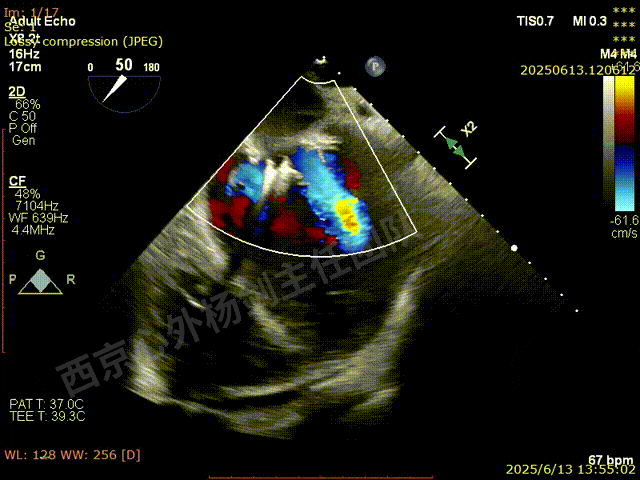

第一枚XTW释放后评估,外侧反流基本消失,内侧仍然有中度以上反流

第二枚XT于第一枚夹子内侧瓣上调整

第二枚XT关闭后评估,trace

二尖瓣平均跨瓣压差1mmHg

释放后评估,反流降至1+,组织桥稳定